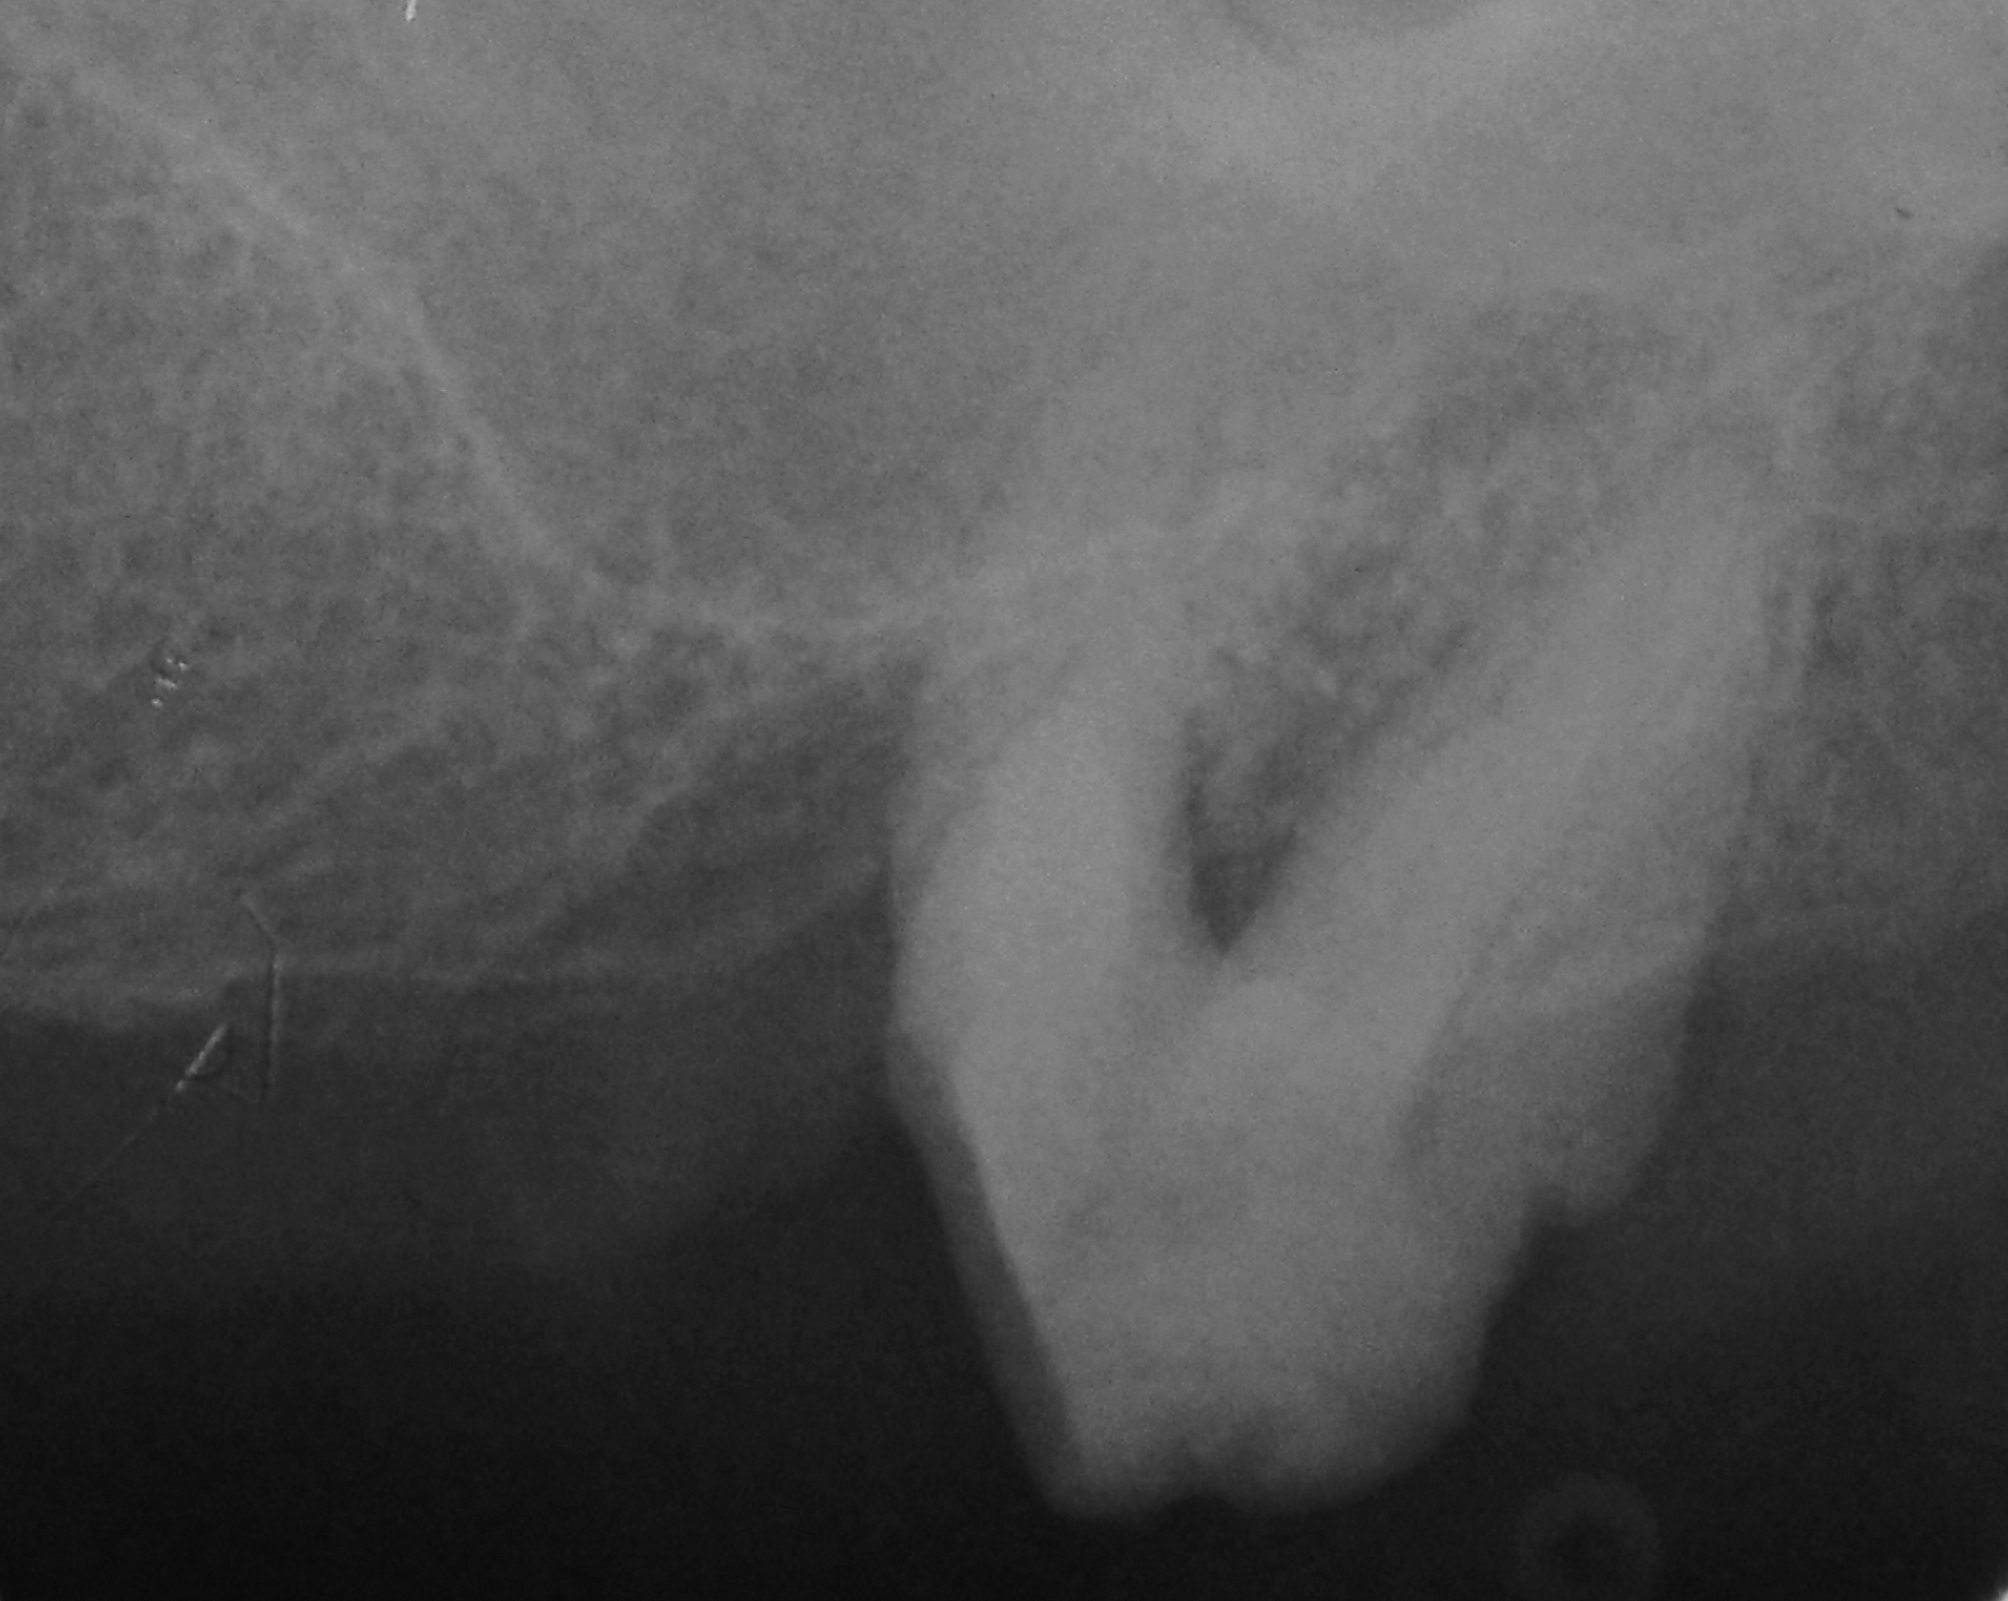

06/06 - Radiograph 5 years post-operative.Treatment of a periodontal bone defect adjacent to an edentulous site using Straumann® Emdogain® - Prof. Dr. P. Windisch

Radiographic view before periodontal regenerative therapy with Straumann® Emdogain®. A deep intrabony defect appeared mesially and distally on the left mandibular first premolar. Pre-surgical probing measured 8 mm. The defect morphology presented as well-contained.